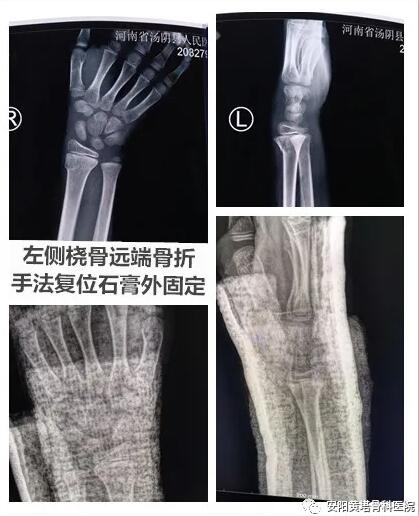

【安陽黃塔骨科醫院】9歲患者左橈骨遠端骨折+左側肱骨遠端粉碎性骨折病例分享

例分享:患者男,9歲,左橈骨遠端骨折,左側肱骨遠端粉碎性骨折;予以左側橈骨遠端手法復位石膏外固定,左肱骨遠端粉碎性骨折閉合復位內固定術,手法正骨與微創技術相結合,避免開刀手術,減少患者痛苦,縮短恢復周期。